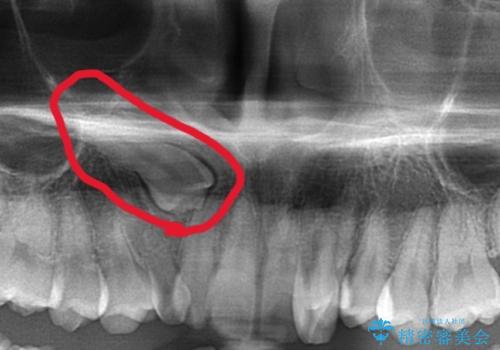

マイクロインプラントについて

インビザライン治療では奥歯の圧下が問題なく行えますが、ワイヤー治療ではマイクロインプラントを使用しなければ奥歯の圧下を行うことが難しいです。